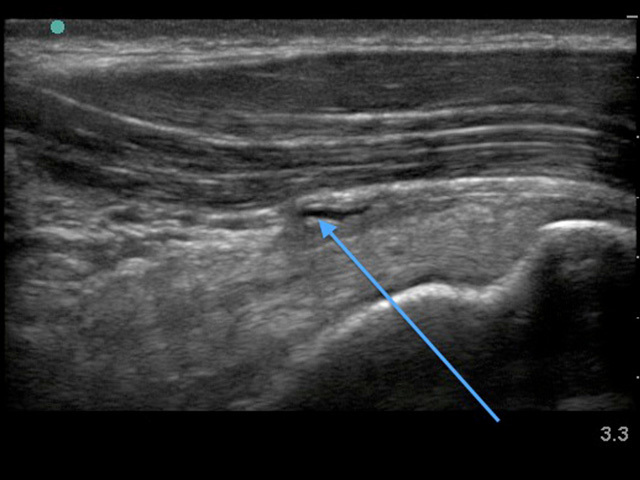

Image - Épaule : Bourse sous-acromiale épaissie

Flèche bleue : Bourse sous-acromiale épaissie